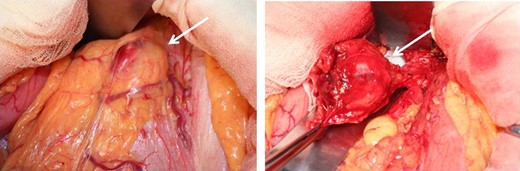

At laparotomy, a well-encapsulated tumor was found in the lesser omentum. It was slightly adhered to the stomach wall but could be removed without difficulty (Fig. 3). There were no obvious lesions of peritoneal dissemination or lymph node metastasis. Therefore, only enucleation of the tumor was performed. The excised tumor, which was 35 × 30 × 25 mm3 in size, had a white cut surface without necrosis or hemorrhage (Fig. 4). Histologically, the tumor was composed of spindle-shaped cells with an interlacing bundle pattern exhibiting microcystic changes and moderate cellularity (Fig. 5a). No mitotic figures were observed. Immunohistochemistry revealed the tumor cells to be positive for c-KIT (CD117) (Fig. 5b), myeloid stem cell antigen (CD34) (Fig. 5c) and α-smooth muscle antigen (α-SMA) (Fig. 5d) and negative for S-100 protein (Fig. 5e). Based on Fletcher’s classification, the tumor was classified as a low-risk GIST originating in the lesser omentum. The patient had an uneventful postoperative course. Presently, the patient is alive, without recurrence, and is doing well 3 years after the surgery without imatinib treatment.

Operative findings. At laparotomy, a well-encapsulated tumor was found in the lesser omentum. It was slightly adhered to the stomach wall but was removed without difficulty.